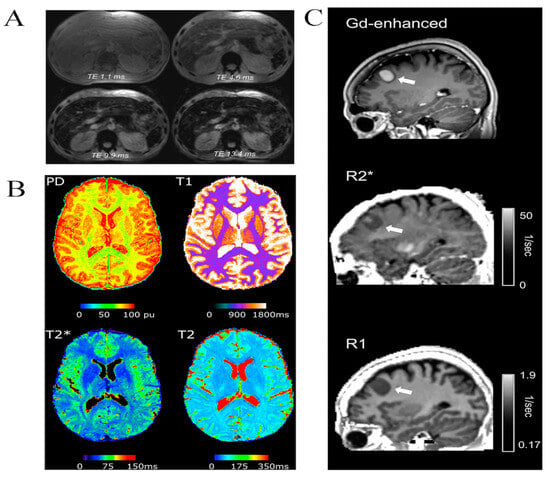

- Filo, S.; Shaharabani, R.; Bar Hanin, D.; Adam, M.; Ben-David, E.; Schoffman, H.; Margalit, N.; Habib, N.; Shahar, T.; Mezer, A.A. Non-invasive assessment of normal and impaired iron homeostasis in the brain. Nat. Commun. 2023, 14, 5467. [Google Scholar] [CrossRef]